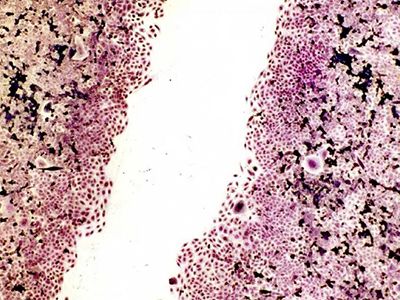

Smásjármyndir af örvuðum og óörvuðum bandvefsfrumum (fibroblastum)

Í annarri frumurannsókn (in vitro studyAn in vitro study is a scientific study conducted in an artificial environment, usually in a laboratory. In vitro studies are used to investigate the effects of substances, procedures or... More) sem framkvæmd var af Dartsch Scientific voru ræktar bandvefsfrumur notaðar til að kanna hvort tíðnisvið sem tækið sendir út gætu haft mælanleg jákvæð áhrif í frumuræktun, samkvæmt viðurkenndum og hlutlægum mæliaðferðum. Örvandi áhrif Mini-Rayone tíðnikubbsins á sáragróanda, sem áður hafa verið skráð af notendum, voru staðfest í þessari frumurannsókn. Áhrifin mældust sem næstum 20% örvun á frumustarfsemi.

Niðurstöðurnar sýna að notkun Mini-Rayone getur til dæmis stutt við og hraðað gróanda.